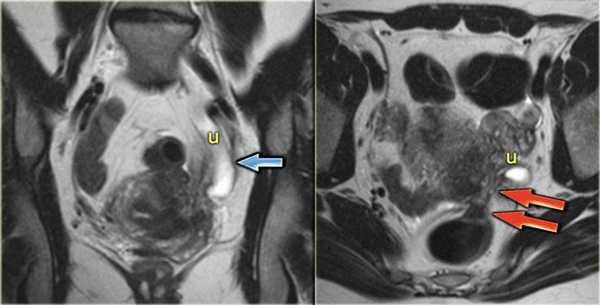

Эндометриоз, осложненный гидронефрозом. На Т2 взвешенных томограммах определяется дилятация левого мочеточника в его дистальных отделах, обусловленная выраженной глубокой эндометриоидной инфильтрацией с поражением левой крестцово-маточной связки и распространением на сигмовидную кишку